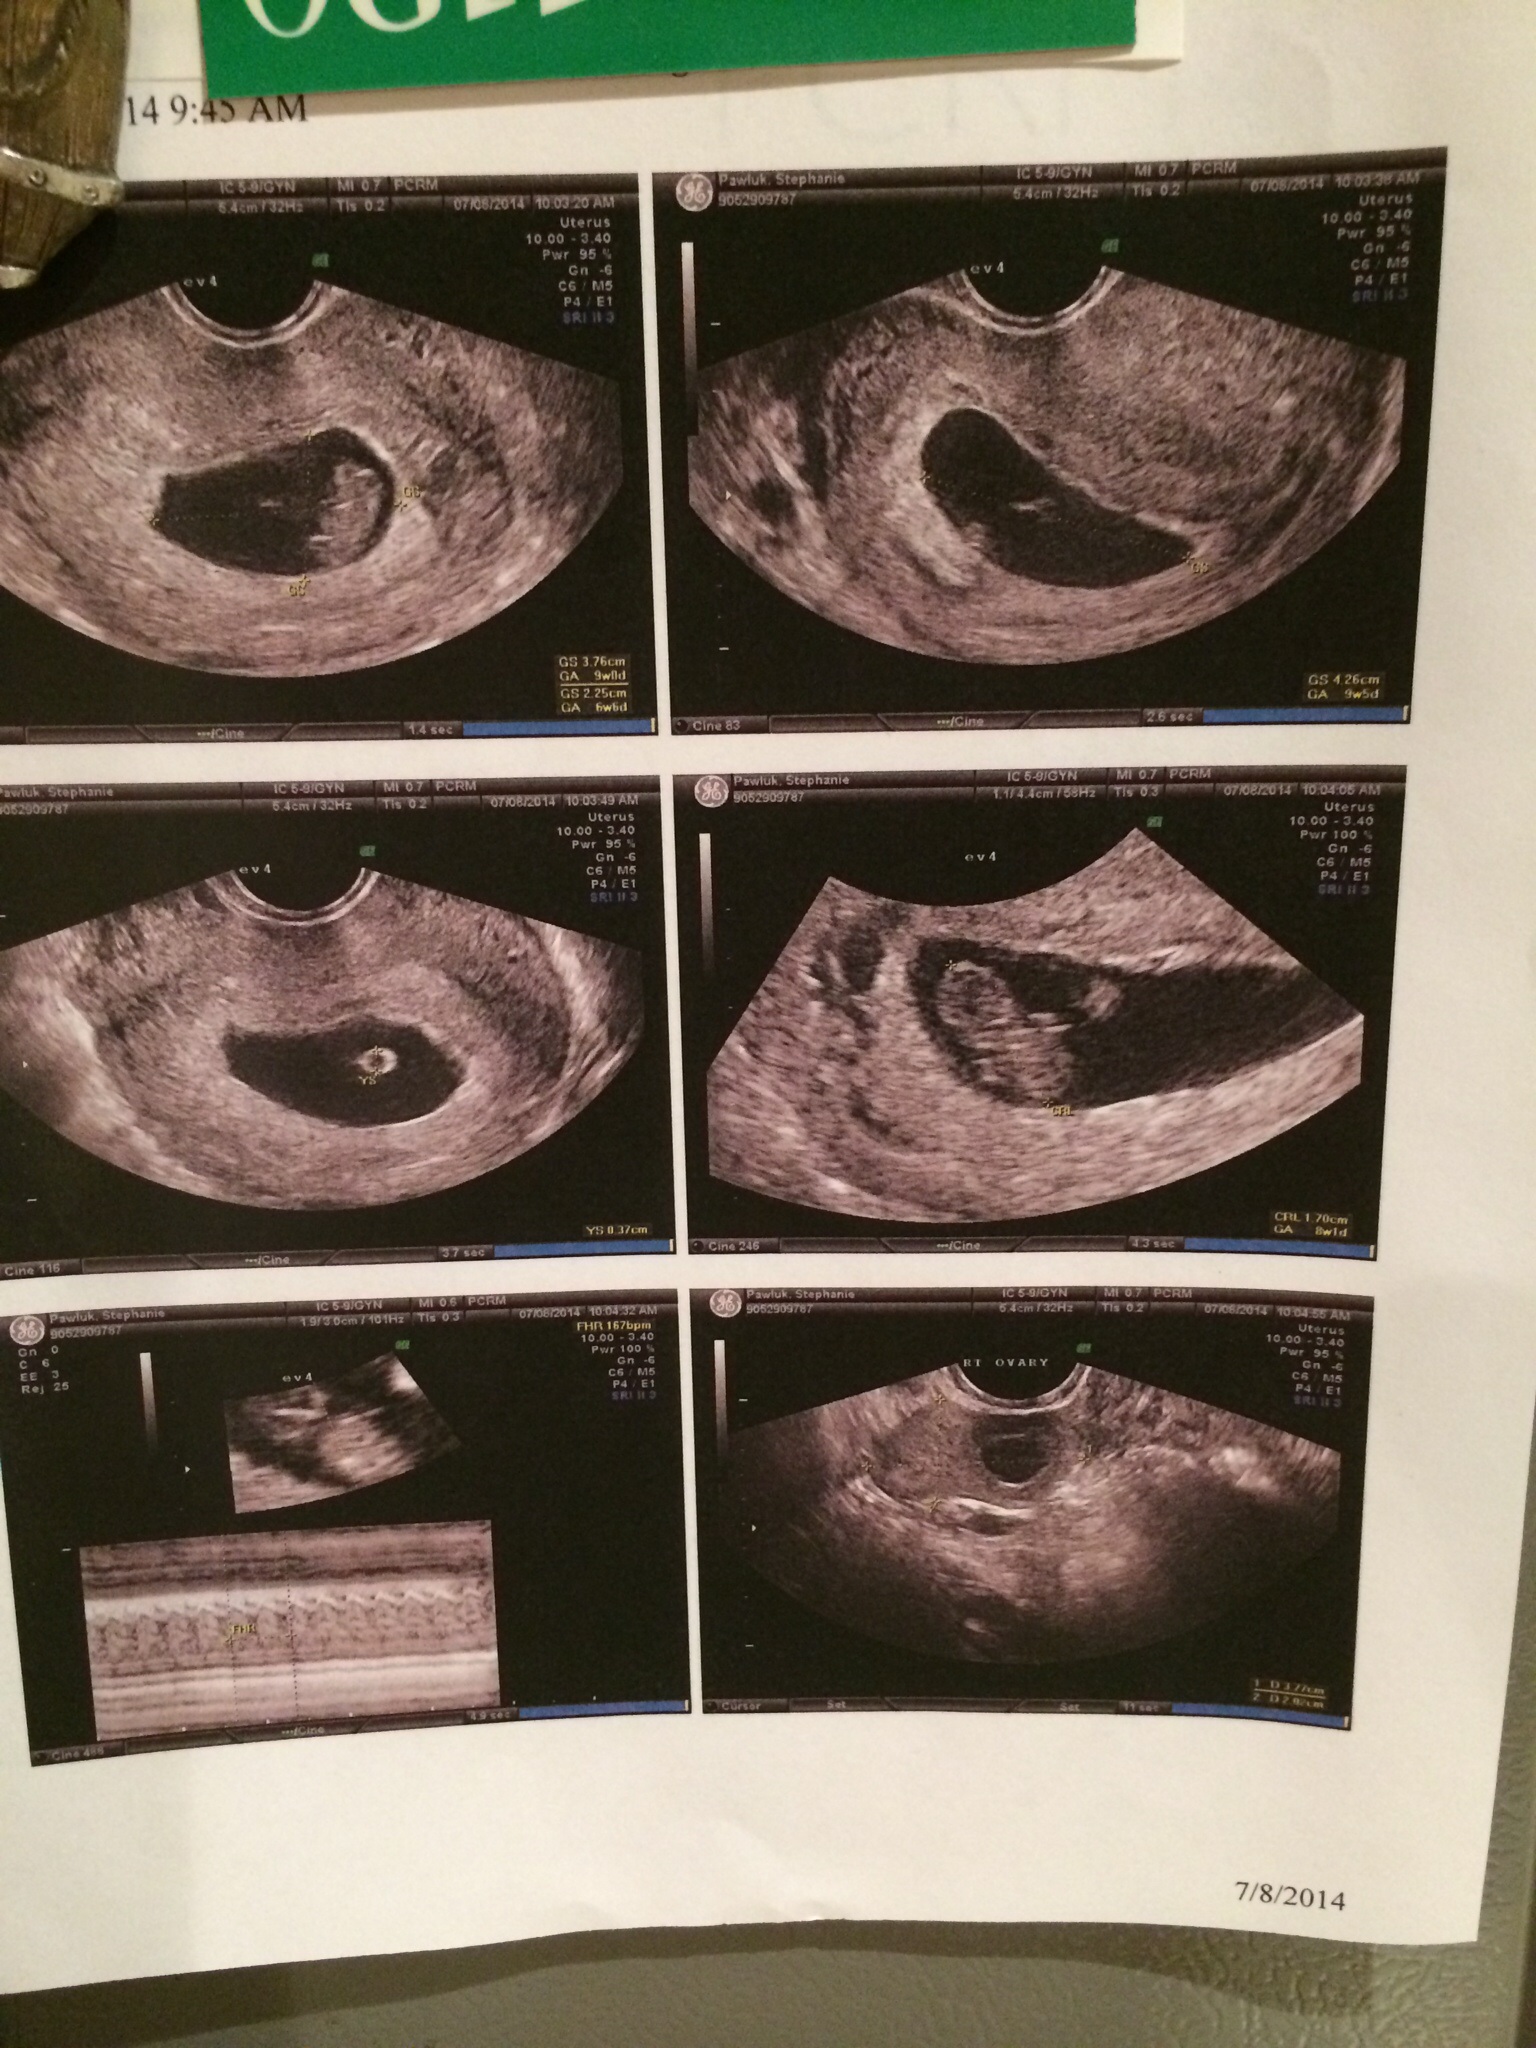

TTC 31\2 years 20 medicated cycles of some kind, 8 failed IUIs (every med combo possible) 5/14/14 IVF # 1, 6dp5dt BFP, Betas 8dp5dt- 67, 14dp -670, 17dp -1761, 20dp-4858, 27dp-28,800 6/11/14 6w3d Twins!!! - EDD Feb 1st

20 medicated cycles of some kind, 8 failed IUIs (every med combo possible)

5/14/14 IVF # 1, 6dp5dt BFP,

Betas 8dp5dt- 67, 14dp -670, 17dp -1761, 20dp-4858, 27dp-28,800

6/11/14 6w3d Twins!!! - EDD Feb 1st